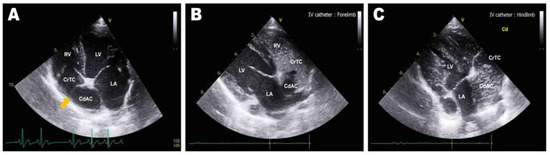

Abdominal radiographs showed severe abdominal distention and a loss of serosal detail (Figure 1); no significant findings were observed apart from these. Transthoracic echocardiography showed an echo-dense, band-like structure within the right atrial chamber, extending from the atrioventricular junction to the free atrial wall (Figure 2A). The right atrium was divided into cranial and caudal chambers. Color Doppler imaging revealed continuous venous blood inflow from the caudal chamber to the cranial chamber through a perforation in the remnant membrane, confirming an abnormal venous blood inflow in the right atrium. An agitated saline study was performed using 3 mL of normal saline to further characterize the flow in the right atrium. Microbubbles were made with saline solution, two syringes, and a three-way stopcock. These were injected in the left cephalic vein and the contrast was noted only in the right atrial cranial chamber and the right ventricle immediately afterward (Figure 2B). When the microbubbles were injected in the left lateral saphenous vein, these reached immediately the right atrial caudal chamber; and some moved into the cranial chamber through a perforated membrane (Figure 2C). This confirmed the presence of a cranial true chamber (CrTC) and cranial vena cava (CrVC) as well as a caudal accessory chamber (CdAC) and caudal vena cava (CdVC). A thoracic computed tomography scan was performed using 30 mL of iohexol contrast agent (Omnipaque, GE Healthcare China). Strong contrast enhancement was observed in the cranial chamber that communicated with the CrVC (Figure 3) during the dextrophase (25 s after contrast injection); in contrast, weak contrast enhancement was observed in the caudal chamber connected to the CdVC. A venous blood inflow obstruction was observed in the right atrium connected to the CdVC, suspected of causing severe ascites. Based on these imaging findings, the patient was diagnosed with CTD, and surgical correction was advised. Both interventional procedures and open-heart surgery can be options for treating CTD. However, considering the potential risk of re-stenosis following interventional treatment, a curative resection involving surgical membranectomy via VIO was planned.

Figure 2. Preoperative transthoracic echocardiography image: left parasternal apical 4-chamber view (A), and right parasternal long-axis 4-chamber view tilted to optimize the view of the right atrium (B,C). (A) Septum-like structure (orange arrow) dividing the right atrium into the cranial true chamber (CrTC) and the caudal accessory chamber (CdAC). (B) Enhancement of the CrTC and right ventricle (RV) via agitated saline microbubbles after intravenous administration into the cephalic vein. (C) Enhancement of the CdAC via agitated saline microbubbles after intravenous administration into the lateral saphenous vein.